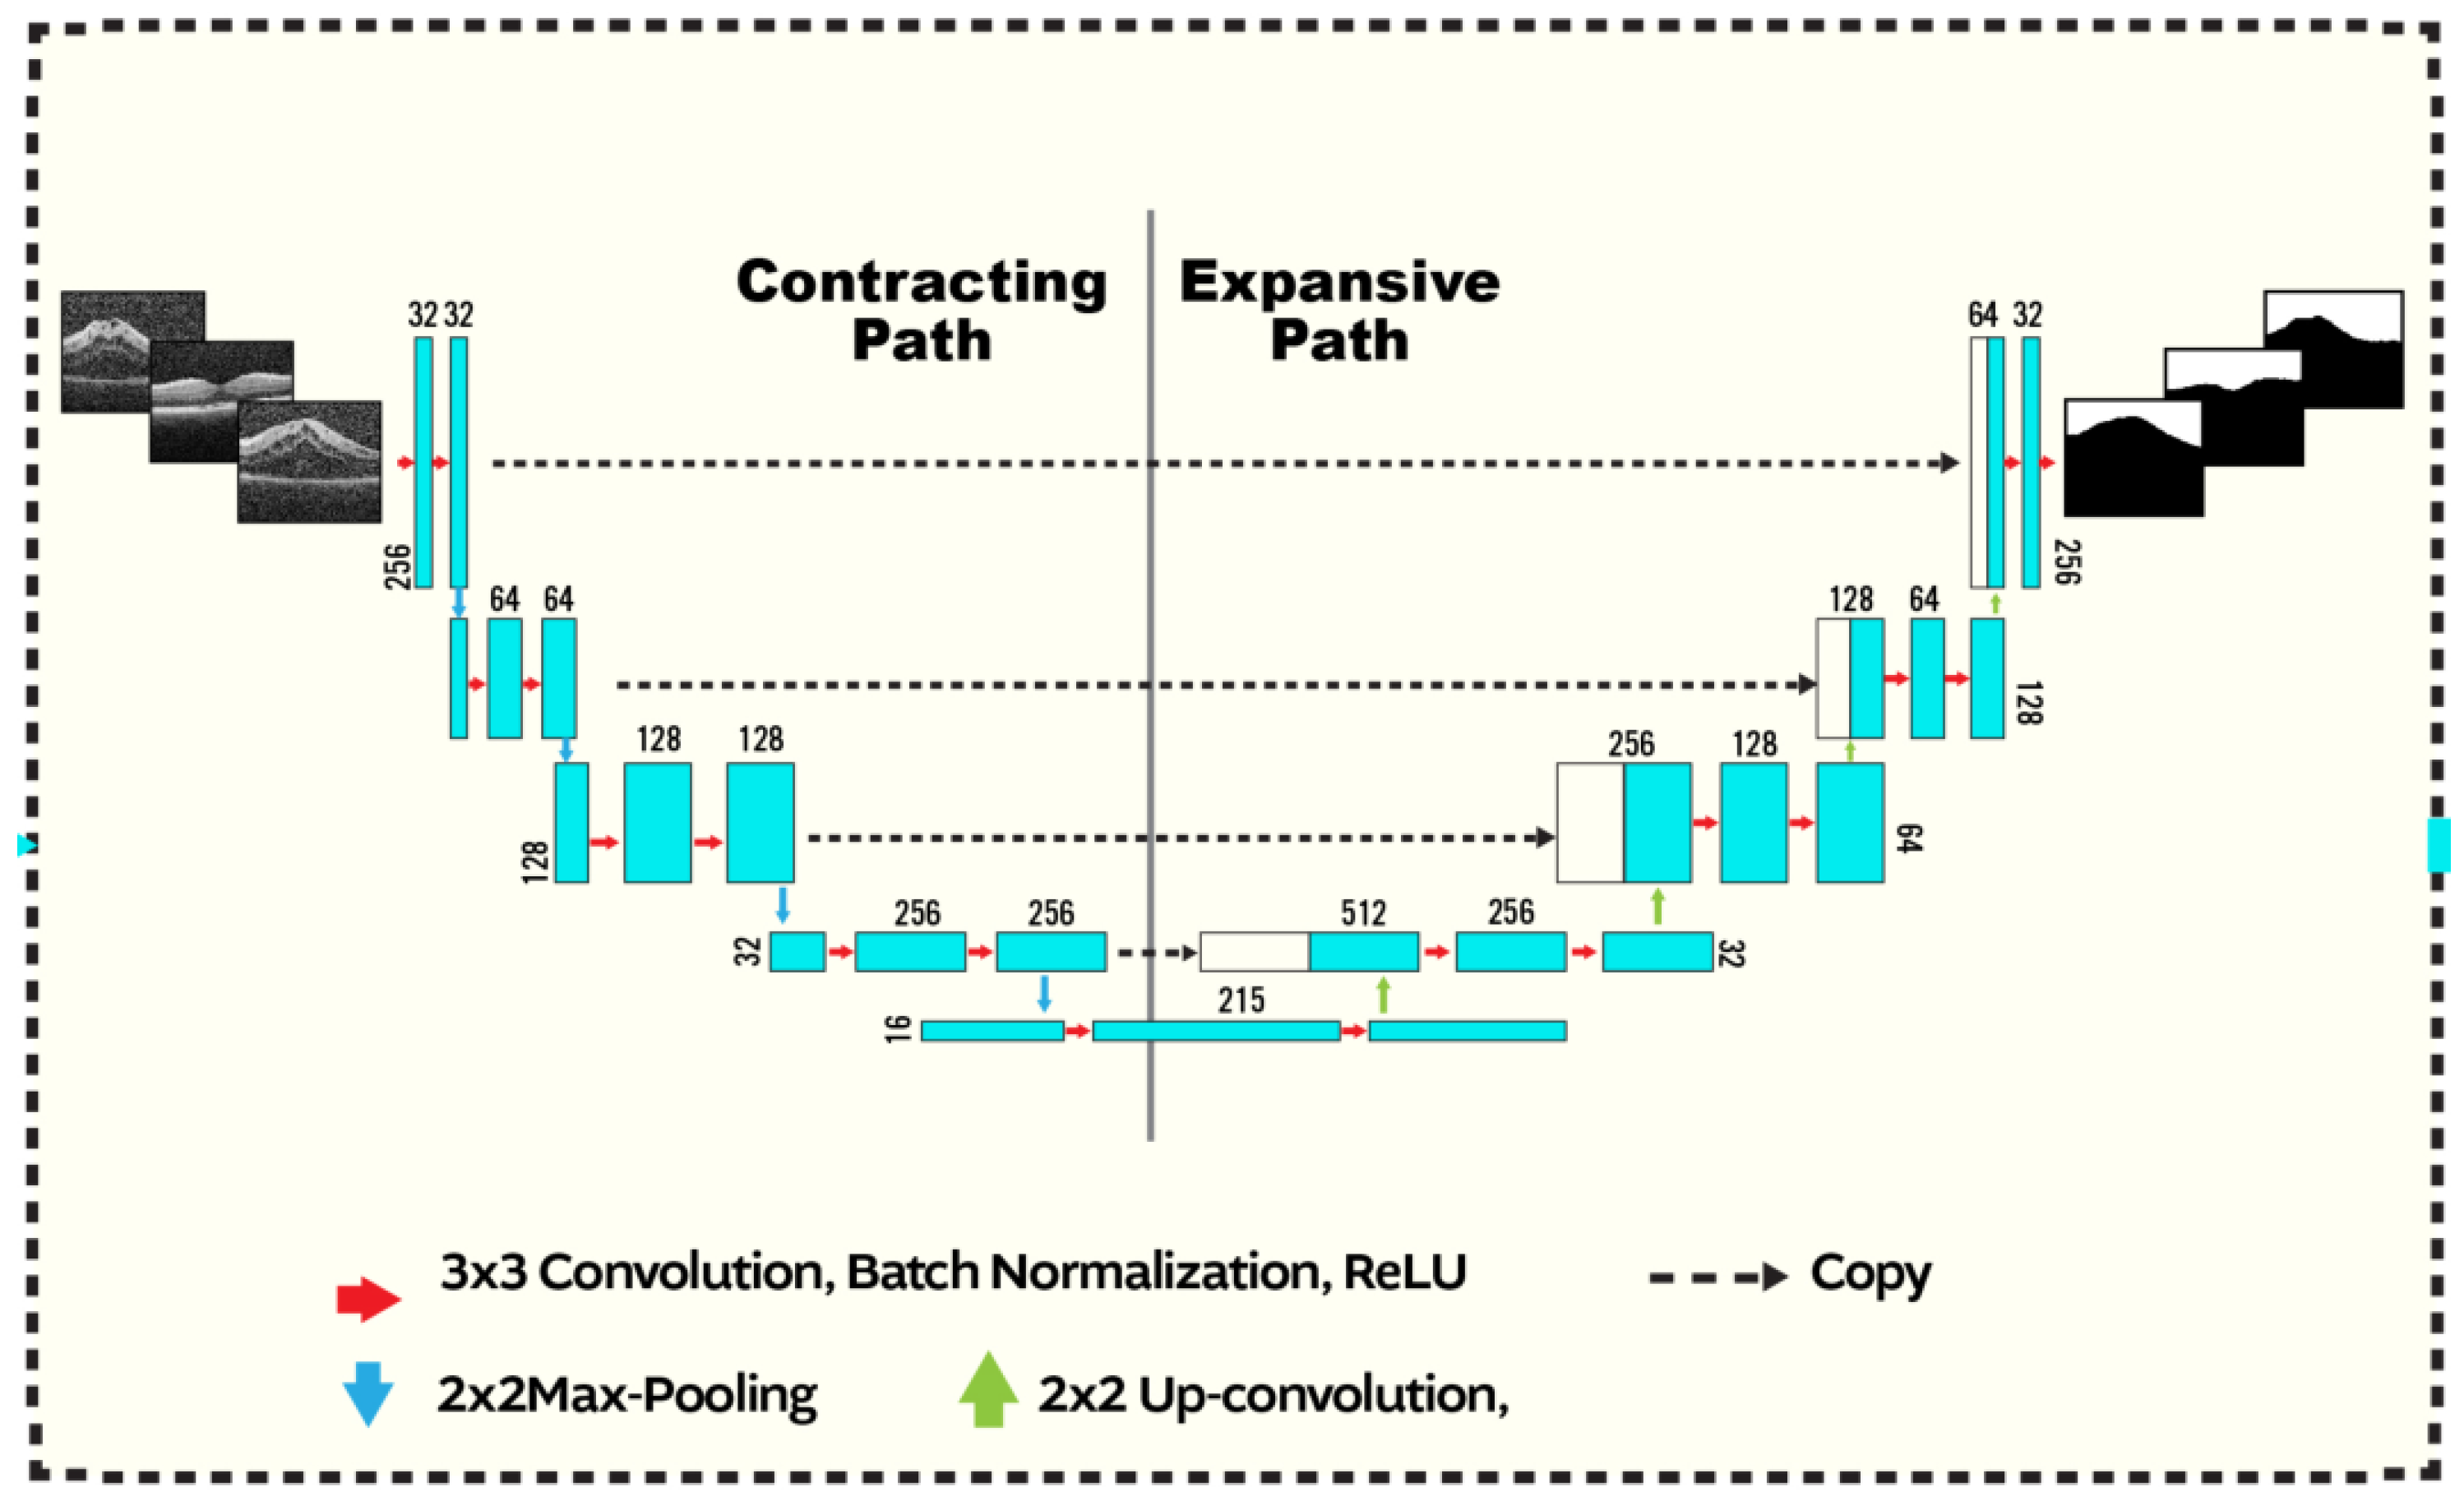

2.1.2. U-Net Segmentation